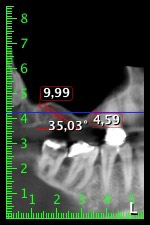

Unos seis meses después de la extracción de las piezas 16 y 14 se realizó una tomografía digital de volúmenes (DVT, Planmeca) para realizar una planificación adecuada y reducir los riesgos al mínimo. En este punto se constató que el hueso no se había regenerado en la cantidad deseada (figuras 2 a 7).

Figuras 2 a 7: Tomografía digital de volúmenes con oferta ósea horizontal reducida.

Con el fin de garantizar una restauración fija en al menos dos implantes, era preciso realizar una elevación del suelo del seno maxilar, tanto en la región 16 como en la región 14. Como en este caso la oferta de hueso residual era extremadamente reducida, fue preciso realizar una retirada ósea relativamente grande. Los procedimientos de retirada ósea grande son invasivos y, además, están asociados a una mayor morbilidad del paciente, llevan más tiempo y resultan más costosos. También es más difícil prever los resultados del tratamiento y el riesgo de fracaso es mayor. Teniendo como telón de fondo estas desventajas, la paciente recibió información sobre la posibilidad de utilizar una alternativa extraíble, pero ella la rechazó firmemente.

Para limitar el aumento a la región 14, se mantuvieron conversaciones con la paciente y se acordó una incorporación oblicua del implante 16 hacia la zona dorso-craneal (figura 8).

Este método permite exclusivamente una solución atornillada en la prótesis definitiva. Para que el puente pueda atornillarse en la zona oclusal, se necesita un pilar angulado (por ejemplo, a 35°) que permita el atornillado perpendicular a la zona de oclusión.

Imagen 8: Tomografía digital de volúmenes del ángulo de inserción para el implante 16.